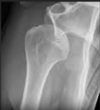

# AP latérale de NEER, votre dx?

luxation antérieure ## Footnote Boule est pas dans le centre du Y Boule dans cage thoracique/poumon = antérieure